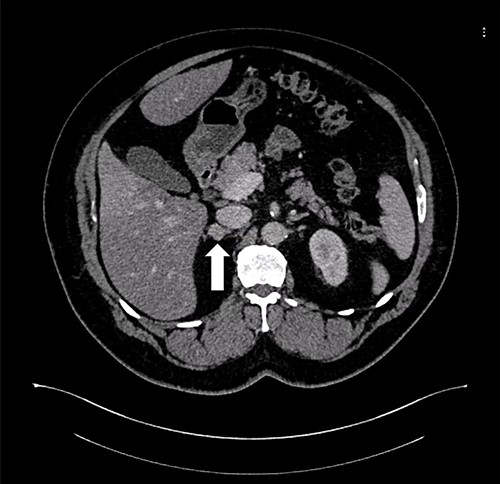

A 37-year-old male, with a BMI of 42 kg/m2, dyslipidemia HTN and gout, presented to our private clinic with progressive weight gain. He also reported an incidental 1.6 cm left adrenal mass on a CECT of the abdomen, which was done in 2014. A repeated CECT showed a larger left adrenal mass of 5 cm, which was lobulated and suggestive of atypical lipid-poor adenoma (Fig. 3). A biochemical workup showed normal serum metanephrine of 50 ng/l (reference <90), normal serum normetanephrines of 90 ng/l (reference <129) and serum morning cortisol of 250 nmol/l. Considering the increasing size of the left adrenal gland and the patient's concerns about it, a LSG combined with LLA was offered to the patient for weight management and diagnosis confirmation of the left adrenal gland.

Axial CT of the abdomen showing the left adrenal mass in Patient 3 (white arrow).